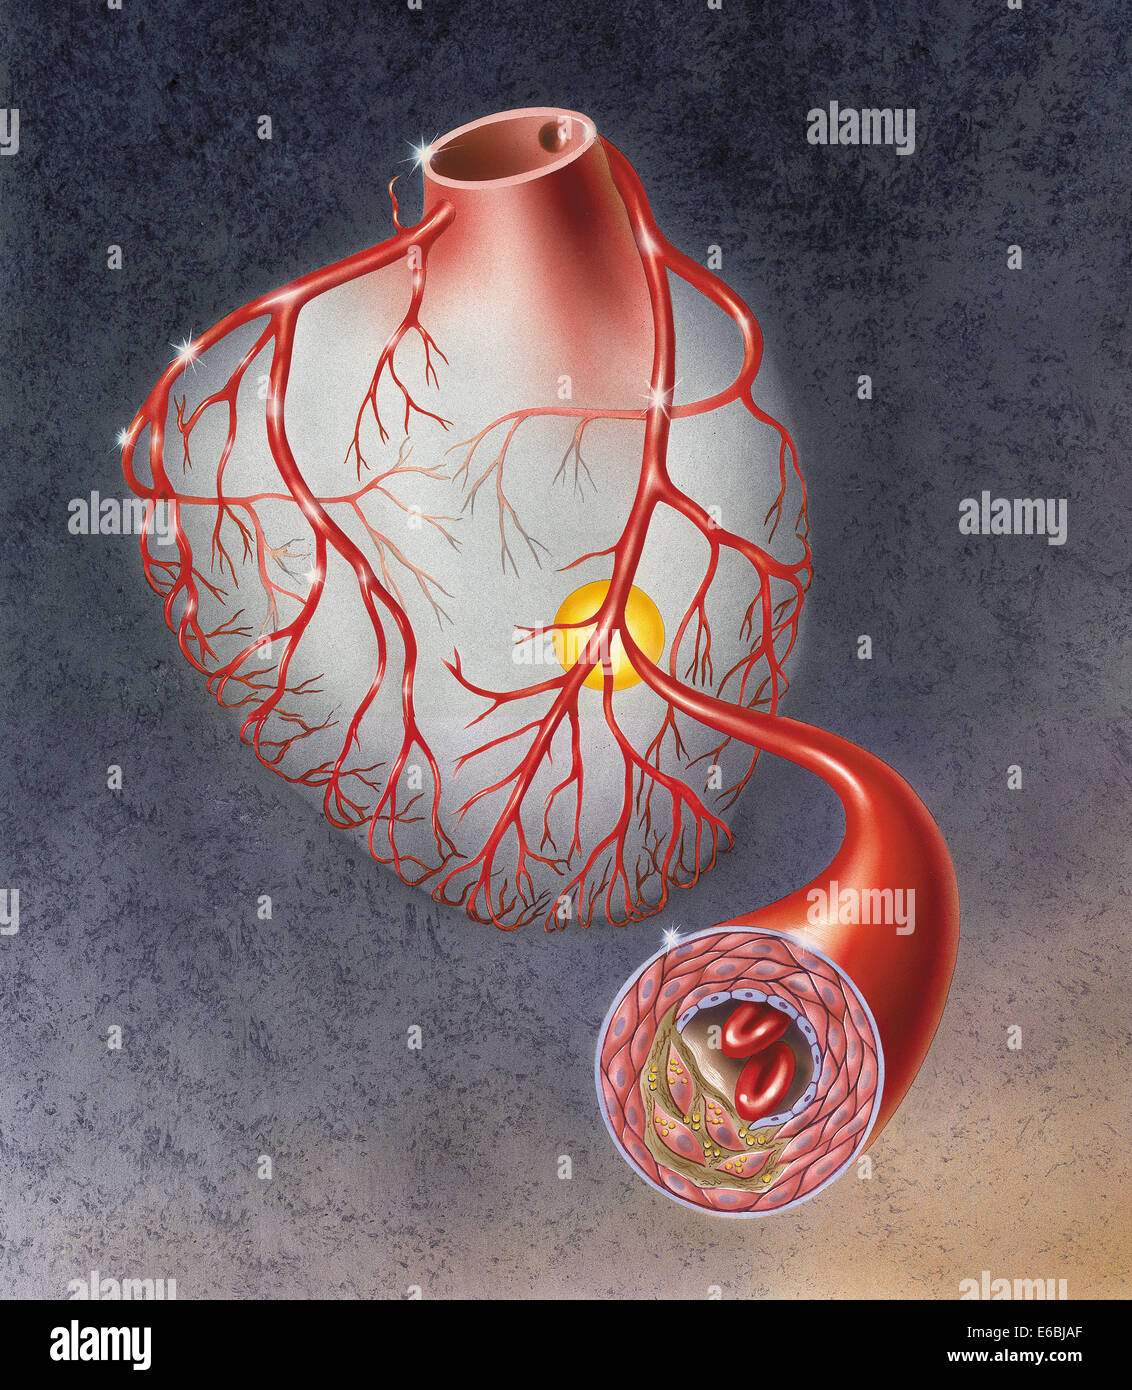

Heart with arteries showing cholesterol in one artery and atherosclerotic plaque in the other. Stock Photohttps://www.alamy.com/image-license-details/?v=1https://www.alamy.com/stock-photo-heart-with-arteries-showing-cholesterol-in-one-artery-and-atherosclerotic-72785305.html

Heart with arteries showing cholesterol in one artery and atherosclerotic plaque in the other. Stock Photohttps://www.alamy.com/image-license-details/?v=1https://www.alamy.com/stock-photo-heart-with-arteries-showing-cholesterol-in-one-artery-and-atherosclerotic-72785305.htmlRME6BJB5–Heart with arteries showing cholesterol in one artery and atherosclerotic plaque in the other.

Arteries on heart showing atherosclerotic plaque in an artery. Stock Photohttps://www.alamy.com/image-license-details/?v=1https://www.alamy.com/stock-photo-arteries-on-heart-showing-atherosclerotic-plaque-in-an-artery-72785287.html

Arteries on heart showing atherosclerotic plaque in an artery. Stock Photohttps://www.alamy.com/image-license-details/?v=1https://www.alamy.com/stock-photo-arteries-on-heart-showing-atherosclerotic-plaque-in-an-artery-72785287.htmlRME6BJAF–Arteries on heart showing atherosclerotic plaque in an artery.